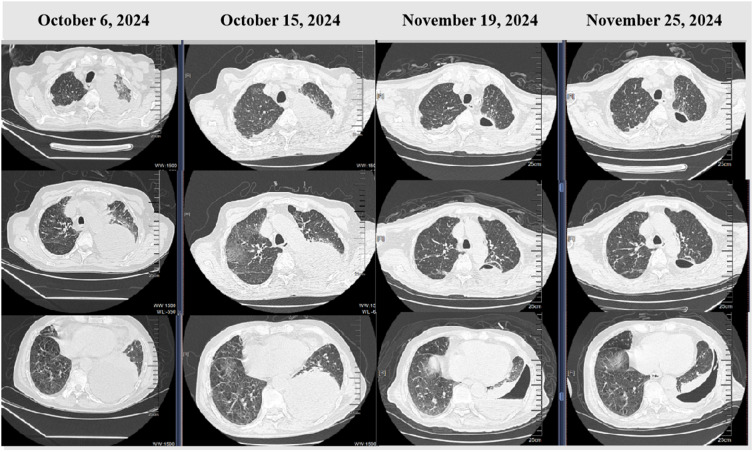

Case presentation: We report a 77-year-old male with a history of chronic smoking and alcohol consumption who presented with a two-month history of cough, sputum production, and progressive dyspnea. His condition rapidly deteriorated with high fever and respiratory failure. Initial antibiotic therapy was ineffective, and multiple cultures of blood, sputum, and pleural fluid were negative. However, mNGS of blood and pleural fluid identified Porphyromonas gingivalis, a well-known periodontal pathogen rarely associated with pulmonary infections. The patient's treatment was adjusted to include targeted anaerobic coverage (imipenem plus vancomycin) alongside chest tube drainage, leading to significant clinical improvement.